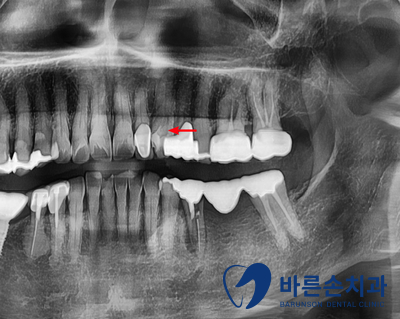

< 초진 사진 >

환자분께서 시큰한 증상를 호소하셨습니다.

송곳니 치아가 치경부에 마모가 심하고, 충치도 있습니다.

충치는 제거를 해보고, 얼마나 깊은지에 따라

치료 방법이 달라집니다.

신경이 노출이 되지 않으면 Resin 치료를 하고

신경이 노출이 되면 신경치료와 크라운 치료를 하셔야 됩니다.

대문니 옆 치아 하나는 레진치료를 하고,

송곳니는 신경관까지 충치가 있어,

신경치료를 진행하여 크라운 치료하였습니다.